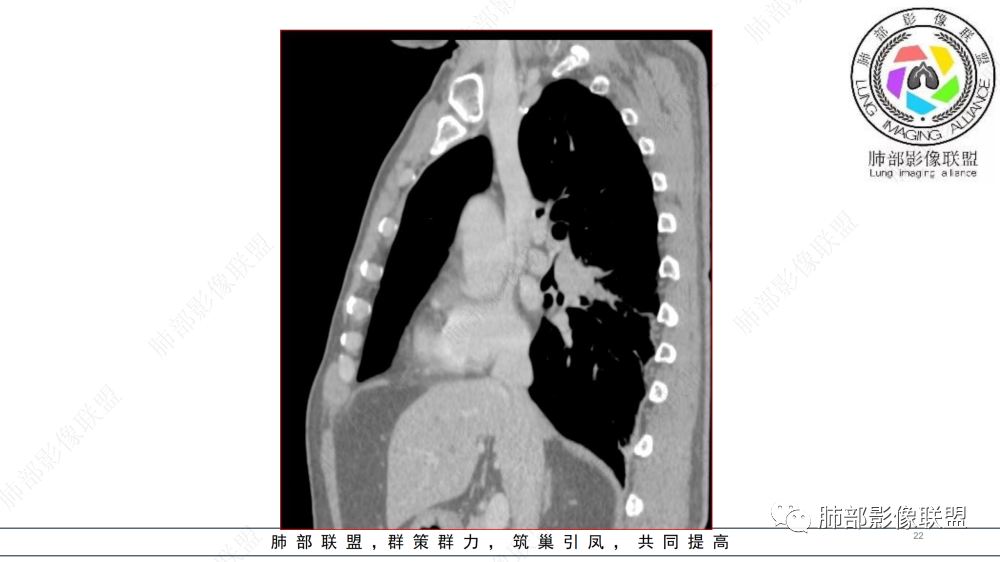

晨读 右肺中间段支气管至下叶支气管狹窄,腔内见软组织肿块,腔内外侵犯,右下肺门软组织肿块形成,不均匀强化,冠状位病变纵径大于横径,远侧肺内阻塞性炎症。定性恶性,考虑腺样囊腺癌或鳞癌

右肺下叶肺门区肿块,向中间段支气管突出,下叶支气管阻塞狭窄,腔内外侵犯,不均匀强化,内可见低密度,冠状位病变沿支气管走行生长,远侧肺内阻塞性炎症,考虑鳞癌,鉴别类癌

中老年男性,右肺下叶背段支气管内新生物,近端可见息肉样突起,远端沿分支支气管生长堵塞,肺门口病灶增强后明显强化,峰值达140hu,远端部分强化不明显考虑粘液栓,考虑典型类癌,鉴别鳞癌。

右肺叶中间段支气管见软组织影不完全阻塞及管腔变窄,向管腔外突破,向下叶背段浸润性生长,见指套及息肉样特点,不均匀明显强化,右肺下叶背段少许阻塞性炎症,肯定恶性肿瘤,小细胞Ca首先,支气管疾病谱恶性肿瘤:类癌,鳞癌,囊腺癌,粘液表皮样癌,与鳞癌,囊腺癌鉴别,支气管镜取材活检可以明确诊断。

晨读:男,57,咳嗽半年,痰中带血3天。胸部CT:右中间段支气管到下叶支气管堵塞性狭窄,管腔内见软组织肿块,壁内外侵犯,长轴沿气道延展,下叶基底多段累及,病变纵径大于横径,远侧可见索条、阻塞性炎症。考虑恶性,腺样囊腺癌?鳞?鉴别N内分泌类、炎性肉芽肿等